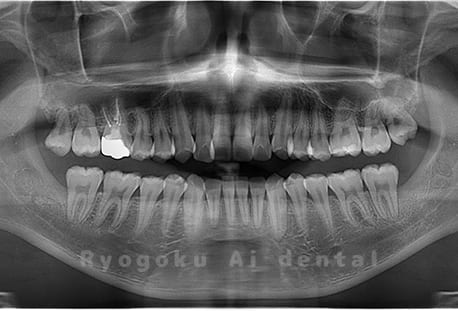

真っ直ぐ生えている親知らず

親知らずが真っ直ぐ生えているタイプです。

このタイプは真っ直ぐ生えていて咬み合わせに問題がなければ、抜歯しないケースもあります。ただし、虫歯になっていたり、痛みがあったり、咬み合わせが悪かったりすると抜歯をおすすめします。